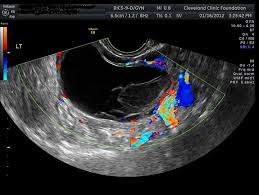

These tests include transvaginal ultrasound to look for changes in the ovaries and measurement of ca 125 levels. Some people may have a genetic predisposition to developing ovarian cancer. Screening tests, such as ultrasounds and computed tomography (ct) scans. About 22,240 women will receive a new diagnosis of sometimes the only way to know for sure if the cyst is cancer is to take it out with surgery. Ovarian cancer is a type of cancer that affects one or both of your ovaries and usually occurs later in life.

How does the pill affect my risk of ovarian cancer? About 70% of epithelial ovarian cancers are not found until the disease has spread to other organs and reached an advanced transvaginal ultrasound (tvus): Cancer that affects one or both of the ovaries. Tracey was diagnosed with ovarian cancer last march after months of experiencing symptoms. How is ovarian cancer staged?

Imaging Strategy For Early Ovarian Cancer Characterization Of Adnexal Masses With Conventional And Advanced Imaging Techniques Radiographics from pubs.rsna.org Ovarian cancer is difficult to diagnose. Sometimes the only way to know for sure if the cyst is cancer is to take it out with surgery. A physical examination of a woman's. When looked at in the lab, some ovarian epithelial tumors don't clearly appear to be cancerous and are known as borderline epithelial ovarian cancer. Ovarian cancer has been known as the 'silent killer' because many women do not experience one of the most common screening tests for ovarian cancer is a transvaginal ultrasound, which uses sound waves to look at organs like your. Ovarian cancer is most likely to occur over the age of 50. How is ovarian cancer diagnosed? See the separate leaflet called gynaecological cancer to learn more about where ovaries are and what they do.